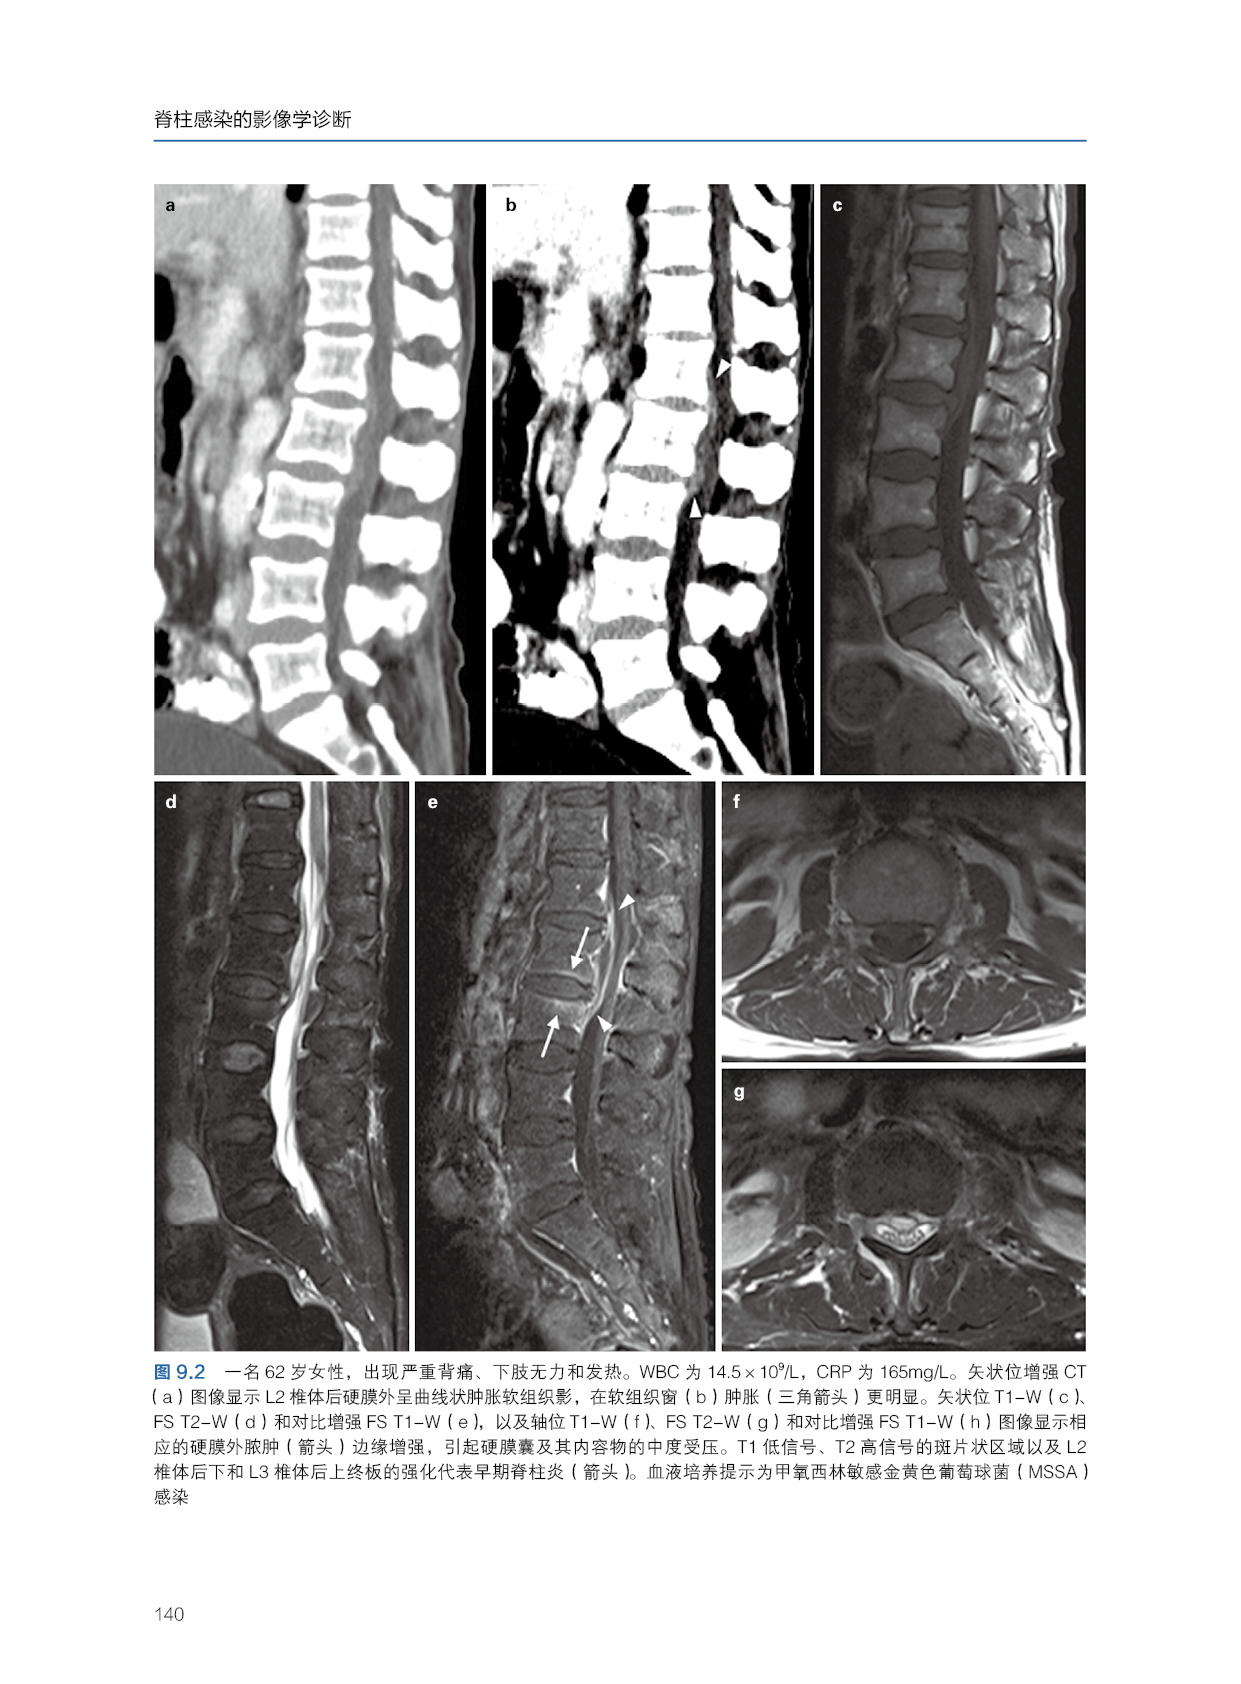

本书主要包含脊柱感染的X线摄片和计算机断层扫描、脊柱感染的经皮穿刺活检、化脓性硬膜外脓肿的影像学、影像学分析(文字分析)、影像学示意图、影像学真实临床影像图片。文字部分的讲解深入浅出,详细且非常便于理解。示意图可以更好地让读者明白和掌握,而临床图片更是将理论与临床实践紧密结合起来。